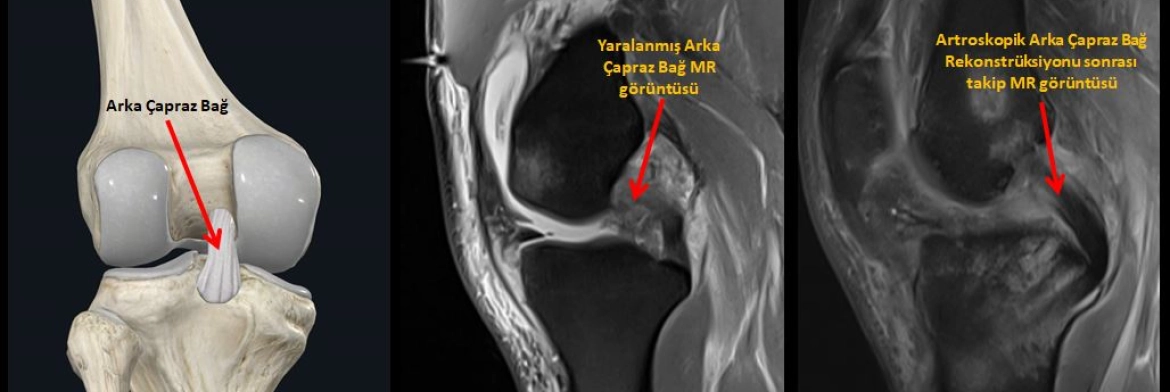

Aşağıdaki resimde, soldaki fotoğrafta arka çapraz bağın yerini, ortadaki fotoğrafta yırtığının MR görüntüsünü, sağdaki fotoğrafta da artroskopik arka çapraz bağ rekonstrüksiyonu ameliyatı sonrası takip MR görüntüsünü görüyoruz.